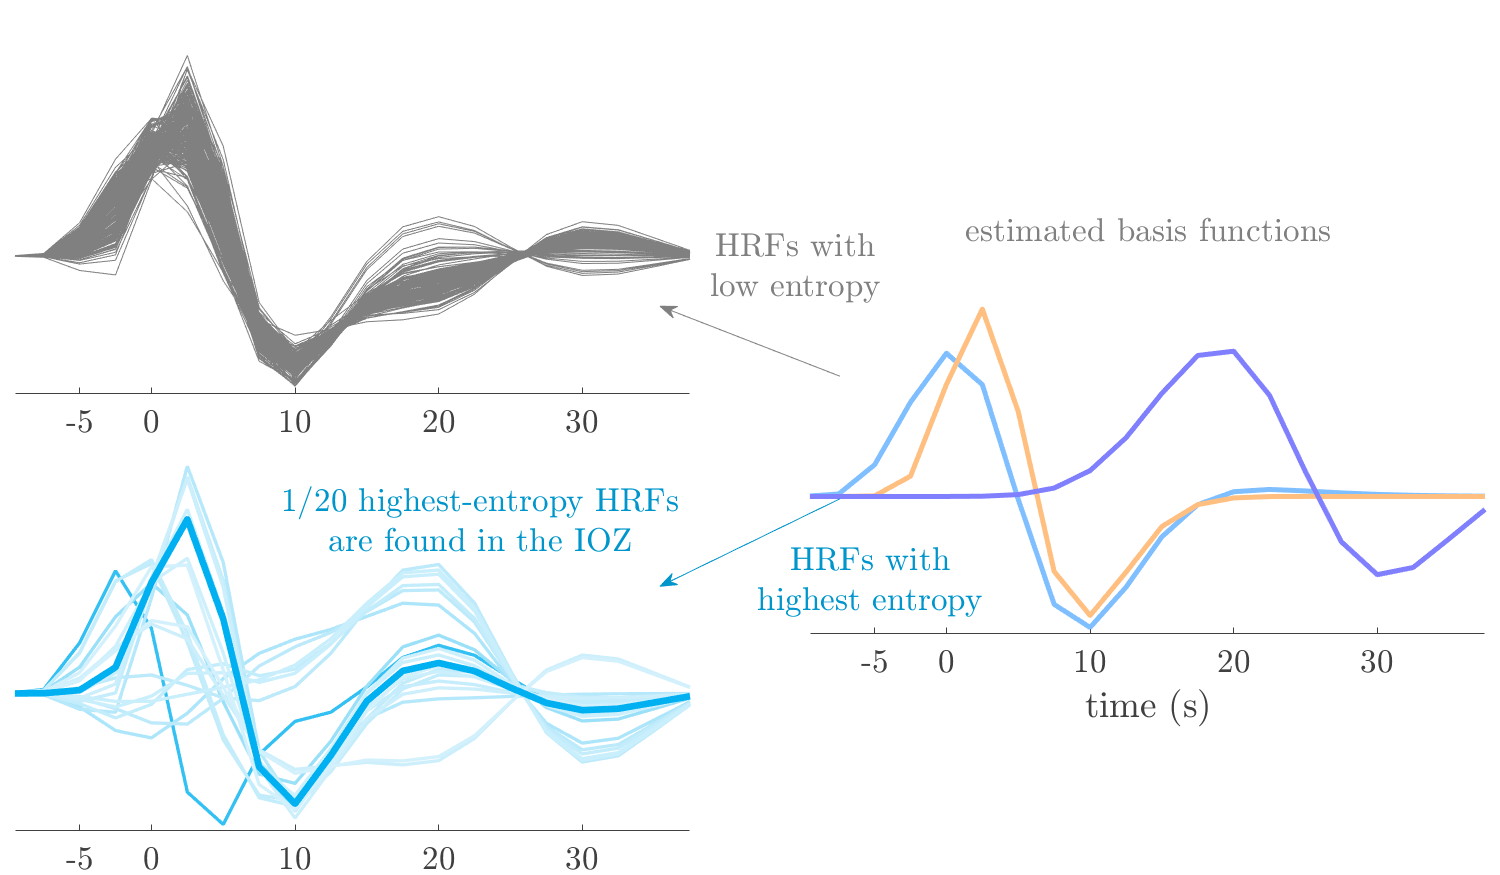

Patient 1

We analyze the solution with sources. Figure 1 shows the EEG signatures and HRF waveforms. One of the sources is highly correlated to the MWF reference (in grey), which was already known from Table B.3. This IED-related source had a typical low-frequency spectrum, which is expected for the typical spike-and-wave interictal discharges. The topography is relatively diffuse, although the highest amplitudes are mostly in the left hemisphere. This is in accordance with the lateralization of ictal onset zone (left temporal lobe, cfr. Table 1). There are some noteworthy observations to be made about some of the other components. The fourth has an unusually sharp spectrum, is mainly localized on two nonadjacent center electrodes, and is sustained for a single period of many seconds Hence, this component likely captured an artifact (of yet unknown origin), although we spotted no large-amplitude changes in the EEG itself. Similarly, the third source is only present at one frontal electrode, and exists in a frequency range above 20 Hz. It might represent a muscle artifact, e.g., due to frowning or twitching of some muscles in the forehead. The HRFs of all ROIs are shown in Figure 1(b). Two of the basis functions seem to have converged to a very similar waveform, which is an unfortunate possibility if two initial HRFs are too close to the same local optimum in their respective parameters. This reduces the expressive power of the basis set, which is clearly visible, since many ROIs have a nearly identical HRF. One of the twenty ROIs with the highest-entropy HRF overlapped the IOZ, although clearly this HRF (bold line) is not among the most dissimilar waveforms for this patient. This is also visible in Figure 2: both the HRF entropy and extremity maps show a small overlap with the delineated IOZ. Despite the good correspondence in the EEG domain, no significant (de)activation of the IED-component is found inside the IOZ.

Patient 2

We analyze the solution with sources, and show the results in Figure 3 and 4. As for patient 1, we found a source which is strongly correlated to the MWF envelope, and which had a mostly low-frequency behavior characteristic for spikes. The topography is mostly uninformative, and does not clearly correspond to the patient’s clinical data. The third source is mostly present at both sides of the head, is very sparsely active in time, and has a high-frequency content: this is most likely an artifact due to the neck muscles. Again, there is one of the highest-entropy HRFs which belongs to a ROI in the IOZ. Now, the waveform is clearly resolved from the other HRFs, through the strong initial dip (before 0 seconds). Such a dip is sometimes observed in HRFs, but its underlying physiological mechanism is not yet fully understood. It is possible that this dip reflects altered vascular autoregulation near the IOZ (cfr. the explanation in the Section 1 of the main text), or a rapid depletion in oxygen due to IED generation (before the IED becomes visible on the EEG). Figure 4 furthermore shows that the IED-related component is significantly active in parts of the IOZ, and deactive in others. As mentioned earlier, this deactivation may or may not be due to errors in sign correction. Interestingly, the ROI with the high alteration in neurovascular coupling is distinct from both the activated and deactivated ROIs.